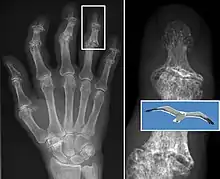

X-ray of erosive osteoarthritis of the fingers, also zooming in on two joints with the typical "gull-wing" appearance

Both primary generalized nodal osteoarthritis and erosive osteoarthritis (EOA, also called inflammatory osteoarthritis) are sub-sets of primary osteoarthritis. EOA is a much less common, and more aggressive inflammatory form of osteoarthritis which often affects the distal interphalangeal joints of the hand and has characteristic articular erosive changes on X-ray.[59]